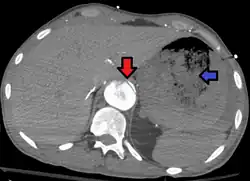

Aorto enteric fistula and aortic dissection of the thoracic aorta. Arrow shows the flap in the aorta. Heterogeneity is blood in the stomach

An aortoenteric fistula is a connection between the aorta and the intestines, stomach, or esophageus.[1] There can be significant blood loss into the intestines resulting in bloody stool and death.[1] It is usually secondary to an abdominal aortic aneurysm repair. The third or fourth portion of the duodenum is the most common site for aortoenteric fistulas, followed by the jejunum and ileum.[2]